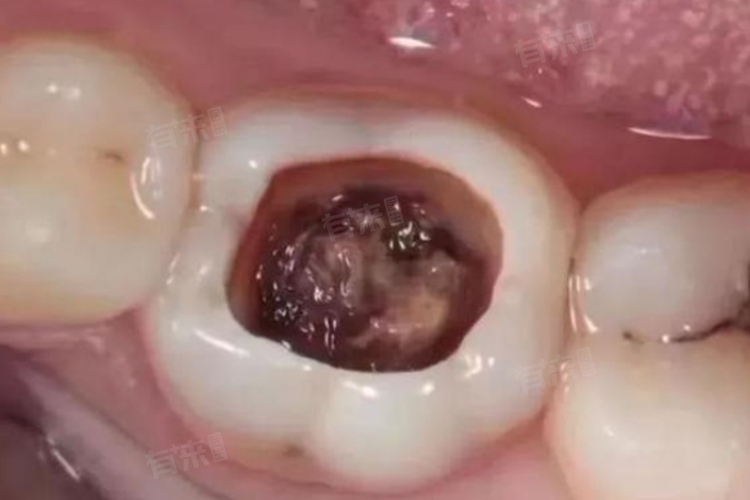

牙齿烂到根部,通常指的是龋齿发展到了较为严重的阶段,已经侵蚀到了牙齿的根部,这种情况在医学上被称为深度龋齿或根尖周炎。不仅会影响患者的咀嚼功能,还可能引发疼痛、感染等一系列问题,可以选择填充治疗等方法处理。

2、根管治疗:若龋齿已经侵蚀到牙髓,引发根尖周炎等炎症,根管治疗将是必要的选择,这一治疗过程包括清除受感染的牙髓组织,对根管进行彻底消毒,并用特殊材料填充根管,以防止细菌再次侵入。治疗完成后,牙齿可能会变得较为脆弱,因此需要佩戴牙冠进行保护。

3、拔牙与种植:对于无法保留的严重龋齿,如牙齿已经大面积腐烂或根尖周病变无法治愈,拔牙可能是唯一的选择。拔牙后,为了保持口腔的完整性和咀嚼功能,可以考虑进行牙齿种植。种植牙不仅外观逼真,而且能够恢复牙齿的正常功能,是许多患者的理想选择。